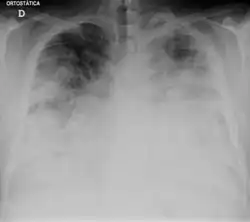

![]() | |

| Chest X-ray of a severe case of legionellosis upon admission to the emergency department | |

Laboratory tests may show that kidney functions, liver functions, and electrolyte levels are abnormal, which may include low sodium in the blood. Chest X-rays often show pneumonia with consolidation in the bottom portion of both lungs. Distinguishing Legionnaires' disease from other types of pneumonia by symptoms or radiologic findings alone is difficult; other tests are required for definitive diagnosis.